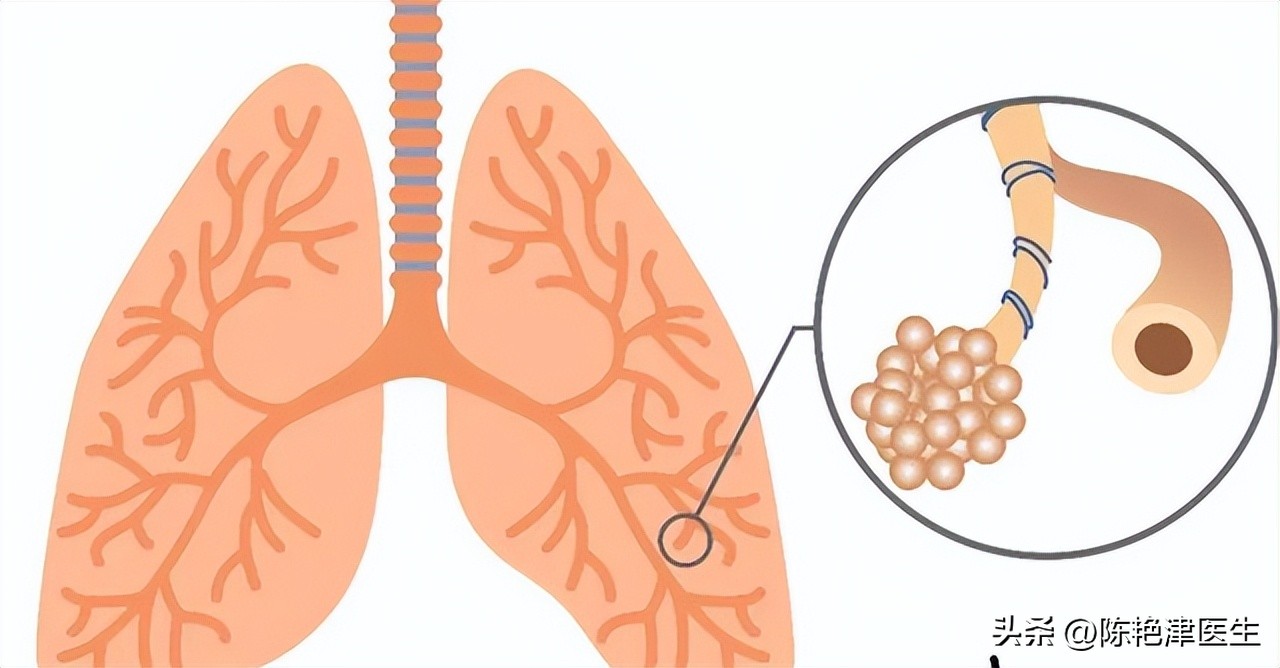

我们吸入的氧气,经由鼻腔、咽喉到达气管。气管像是树干,会分出无数的枝干,形成 各级支气管 。气管每次发出分支,管道直径都会越来越细,每个分支都会在最末端会形成 肺泡 结构。

肺泡的结构像是蜂窝上的 蜂房 ,是一个一个的小圆球组成的,形态类似 葡萄样 聚集在一起。正常的肺泡平均直径约为0.2 毫米,正常人约有3-4 亿个肺泡【1】,是肺功能的基本单位,是进行 气体交换 的主要部位。